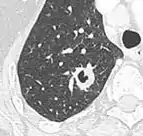

Lobulated nodule.[9]

Spiculated lung nodule.[9]